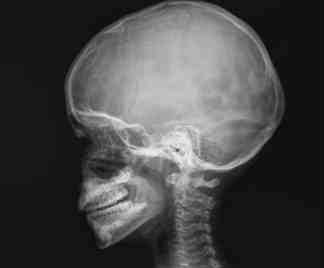

- Prueba: Rx de cráneo frente y perfil o cavum.

- Perfil: Decúbito supino o prono, giraremos la cabeza hacia un lado y sujetaremos contra la mesa una talla doblada pero sin arrugas estirada siguiendo la línea meato-orbital.